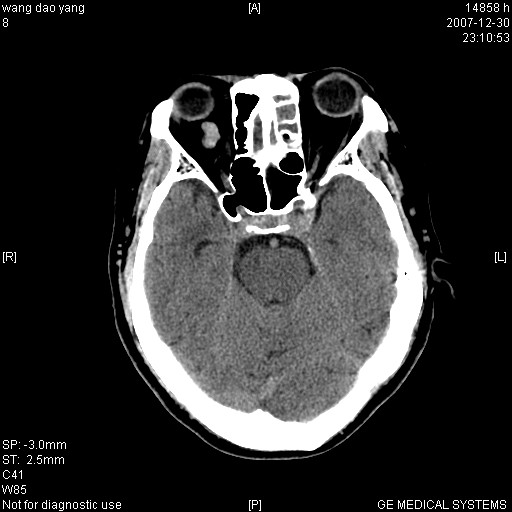

因外伤做ct

1。左侧筛窦蝶窦少量积液,2。右眼眶视神经鞘瘤可能性大,建议增强一下

肌圆锥内占位性病变,血管瘤可能性大。

1 病灶位于肌圆锥内,从第一帧看,和视神经关系不紧密。

2 病灶边界光整,形态欠规则。

3 病灶密度明显高于同层面的正常软组织。

外伤的话首先考虑球后血肿!!

肌圆锥内类软组织密度影,边缘清楚,位于视神经上方,考虑:炎性假瘤可能性大.

建议:强化扫描.

病灶形态不规则,临床有外伤史,支持考虑:球后血肿!!!

考虑右侧视神经脑膜瘤或血管瘤,建议增强进一步检查。

考虑右侧视神经脑膜瘤或视神经胶质瘤,建议增强进一步检查鉴别。

考虑右侧视神经鞘瘤,脑膜瘤或纤维瘤。

球后肌锥内小团块状软组织密度影(性质待定);建议:行ct增强扫描或mri检查。